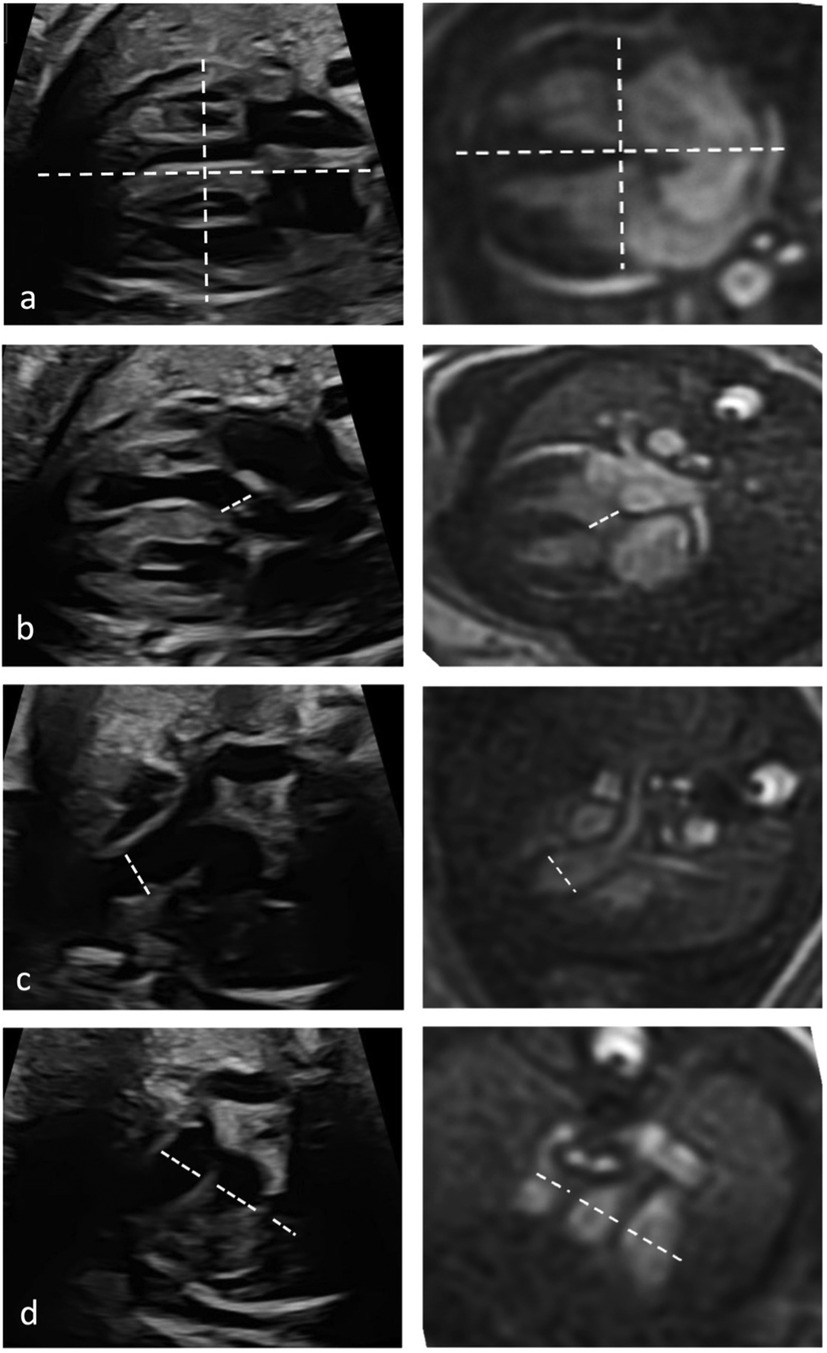

Image quality score of fetal cardiovascular MRI, assessed for each of the five axial views per fetus, was high with a mean score of 2.8 ± 0.8 (score 4 in 15.9%, score 3 in 53.8%, score 2 in 19.3%, score 1 in 11%) (Figure 1).

Figure 1

MR diagnostic quality of each anatomical structure/morphology assessed from the five axial views revealed highest scores for cardiac topography and situs and lowest scores for cardiac valves (Figures 2, 3).

Figure 2

Figure 3

Quantitative evaluation of diameter measurements in the five axial views showed no differences between fetal cardiovascular MRI and fetal echocardiography (Table 3). Examples of measurements are provided in Figure 4.

Figure 4